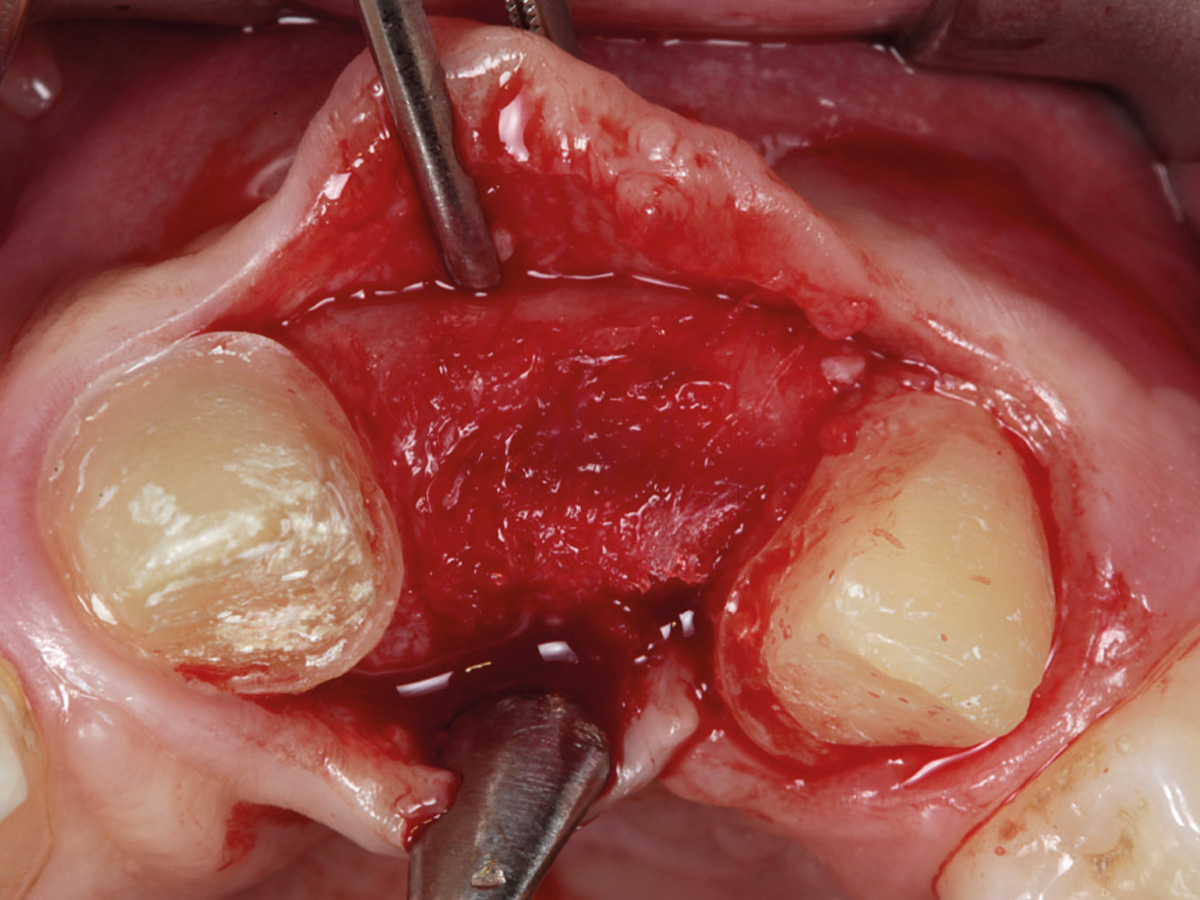

Abbildung 10

Regenerierter Bereich nach Lappenbildung. Gewebe gut durchblutet, Reste der Lamina sichtbar.

Abbildung 11

Ein Implantat mit 3,8 mm (Ø) konnte in seiner korrekten dreidimensionalen Position eingebracht werden.